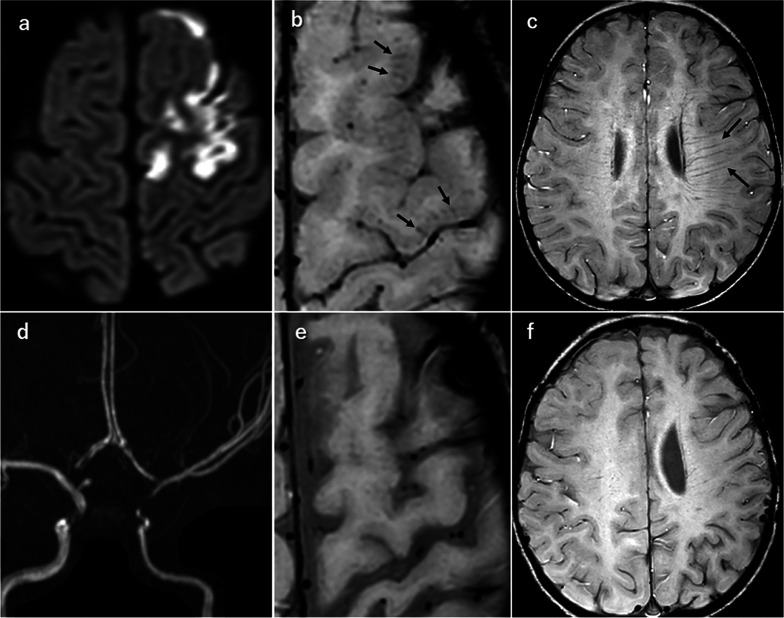

我们观察到一种新的 SWI 发现--"皮质刷状征",它代表了急性脑梗塞患者皮质中突出的静脉结构,无论患者是否患有莫亚莫亚病和脑静脉血栓形成。所有病例的皮质刷状征均在后续的 SWI 检查中消失。皮质刷状征有助于了解急性期皮质静脉结构的病理生理学。

We observed a new SWI finding, "cortical brush sign," that represents prominent venous structures in the cortex of patients with acute cerebral infarct with or without moyamoya disease and cerebral venous thrombosis. The cortical brush sign disappeared on follow-up SWI in all cases. Cortical brush sign may help to understand the pathophysiology of venous structures in the cortex at acute phase.